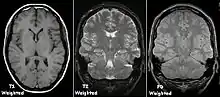

| صدي المغزل | التوقيت الرأسي | T1 | قياس الاسترخاء الطولي باستخدام وقت التكرار ووقت الصدى القصيرين. |

كما يُمثل الأساس والمقارنة للتتابعات الأخرى. |

| التوقيت الأفقي | T2 | قياس الاسترخاء المستعرض باستخدام وقت التكرار ووقت الصدى الطويلين. |

| كثافة البروتون | PD | وقت التكرار الطويل ووقت الصدى القصير.[4] | جرح واعتلال المفاصل.[5]

|

يرجع كل نسيج إلى حالته الطبيعية من التوازن بعد إثارته بعمليات الاسترخاء المستقلة لكل من التوقيت الرأسي (الاسترخاء الطولي؛ ويتمثل في المغنطة الطوليه -في نفس- لاتجاه المجال المغناطيسي الثابت)، والتوقيت الأفقي (الاسترخاء المستعرض؛ المغنطة المستعرضة لاتجاه المجال المغناطيسي الثابت). وللحصول على صورة موزونة بالتوقيت الرأسي فإنه يُسمح باستعادة المغناطيسية قبل قياس إشارة الرنين المغناطيسي عن طريق تغيير وقت التكرار، ويُعتبر هذا الوزن مفيدًا لتقييم القشرة الدماغية، وتحديد الأنسجة الدهنية، وتوصيف آفات الكبد البؤرية، أو بعبارة عامة يُعتبر هذا الوزن مفيدا عند الرغبة في الحصول على معلومات شكلية حول النسيج وكذلك عند التصوير التالي للصبغة. أما في حالة الرغبة في الحصول على صورة موزونة بالتوقيت الأفقي، فإنه يُسمح بتحلل المغنطة قبل قياس إشارة الرنين المغناطيسي عن طريق تغيير وقت الصدى، ويُعد هذا الوزن مفيدًا في الكشف عن الوذمات والالتهابات، وكشف آفات المادة البيضاء، وتقييم التشريح البؤري للبروستاتا والرحم.

يتمثل العرض القياسي لصور التصوير بالرنين المغناطيسي في تمثيل خصائص السوائل في الصور بالأبيض والأسود، حيث تظهر الأنسجة المختلفة على النحو التالي: